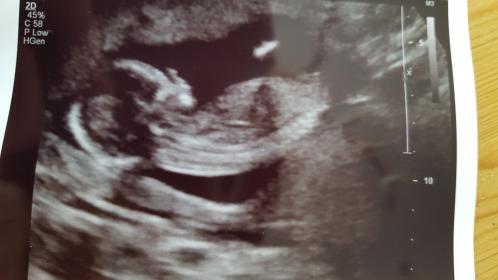

This is from My 14 week scan and the tech didnt want to

Talk about the gender of the baby.

İ really want it to be a girl so i Hope You can help me with the guessing 😊😊

Tricky, I don't think the nub is properly visible in these pics. Do you have more, or a video or a potty shot?

That last pic *might* be showing a girly nub, but I really don't want to give you too much hope. You could post the other pics if you have any more, you never know if there is a better nub shot among them.